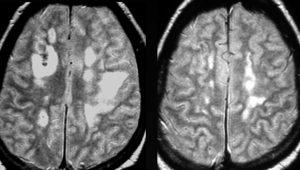

これは1990年代の古い例ですがリンパ腫の増大が早いことをお見せします。左側のはTHP-COPという化学療法をする前のものです。真ん中のは化学療法から4日目で,腫瘍は小さくなりました。でも,2コース目の化学療法の直前(4週間後)にもう一度MRIをしてみたらすごく大きくなっていました。この化学療法は効いているのだか効いていないのだか判らないことになります。化学療法を行なうならとても強い薬剤を使わなければなりませんし急がなければなりません。